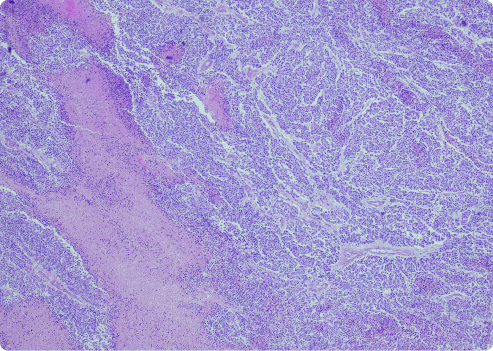

This variant has dense fibrous tissue and fewer cells. Desmoplastic cells are hard to identify. They lack clear patterns. These types of mesothelioma cells form dense nodules of connective tissue in tumors. This can make diagnosis more difficult.

- At least 50% of the tumor consists of nodules with dense fibrous tissue.

- Areas with increased cell activity show sarcomatoid features.

- Neoplastic spindle cells have spread to the lungs or chest wall.

- There is evidence of metastasis to nearby fat tissue, skeletal muscle or the lungs.

- The p53 tumor suppressor gene protein is present.

When desmoplastic mesothelioma spreads, it can seem less aggressive. This makes it easy for doctors to mistake the cells for benign fibrous tissue. Imaging scans, like CT or MRI, can be very helpful for pathologists. It can make it easier to spot the spread of tumors and correctly diagnose tough cases.